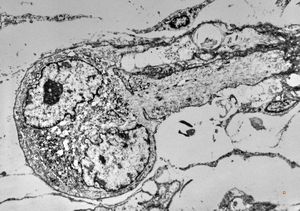

F,25y. | metachromatic leukodystrophy - n. suralis

F,8y. | metachromatic leukodystrophy - n. suralis

F,25y. | metachromatic leukodystrophy - n.suralis